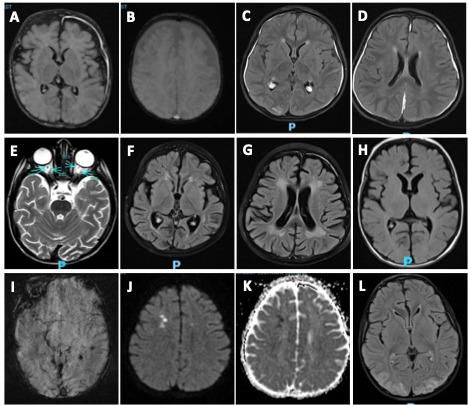

MRI scans were obtained in 20 of 22 (90.9%) patients at a median of 17 days from symptom onset with overlapping findings. Patchy T2 FLAIR prolongation was noted in 17 (85%) patients with 6 (35.2%) patients having T2 FLAIR prolongation in gray matter. Other MRI abnormalities included diffuse brain atrophy 8 (40%), microhemorrhage 3 (15%) and diffusion restriction 3 (15%). MRI abnormalities in pediatric pHLH patients are shown in Figure 1.

T2 FLAIR prolongation in gray matter was frequently observed, possibly due to impaired mitochondrial oxidative phosphorylation or global hypoperfusion.40 Brain atrophy, microhemorrhages, white matter abnormalities, and leptomeningeal enhancement were also noted, consistent with prior findings.14,41 Higher CSF WBC count in patients with pHLH compared to sHLH may be due to difference in pathophysiology. The underlying genetic mutation in pHLH can produce a more pronounced aberrant activation and infiltration of macrophages and microglia in the CNS, resulting in higher degree of CSF pleocytosis.